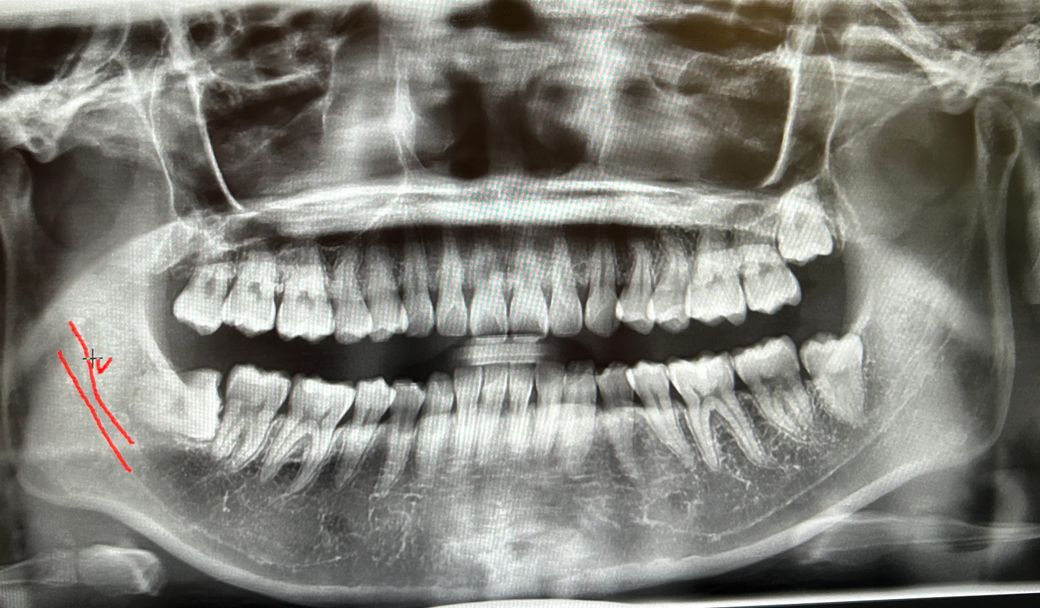

왼 쪽 하악이 신경이랑 가까워서 꽤나 속썩였는데요, 왼쪽 해결하고나니 오른쪽이 눈에 들어옵니다..

오른쪽 상/하악 신경이랑 많이 가까울까요...?ㅠ

정확한건 CT를 찍어보고 판단을 하겟지만 엑스레이 상으로는 신경관과 거리가 어느정도는 잇을것같으니 너무 걱정하지마세요.

오른쪽 아래에 기울어진 사랑니 치아의 경우에는 신경관과 치아는 파노라마 상으로도 띄어져 있기 때문에 신경 손상의 가능성이 클 것으로 생각되진 않습니다.

사랑니와 신경 사이에는 거리가 꽤 있어보입니다. 크게 걱정하지 않아도 될 것으로 보입니다.

사진에서 빨간색으로 표시된 부위가 본인 몸에서 오른쪽이며 하치조신경과 거리가 떨어져 있습니다. 사진에서 반대편 본인 몸에서 왼쪽의 경우 하치조신경관과 약간 겹쳐 있습니다.

신경과의 거리는 어느정도 있고 사랑니 뿌리가 모여있어서 괜찮을 것 같습니다. 다만 맹출 방향 자체가 바로 앞 어금니에 수평으로 붙어있어서 뽑는것이 좋아보이긴 합니다.

보통 발치 시 고려되는 해부학적 구조물은 아래턱의 신경관이고요. 근접하긴 했지만 조심해서 빼면 큰 문제는 없을 것 같습니다.